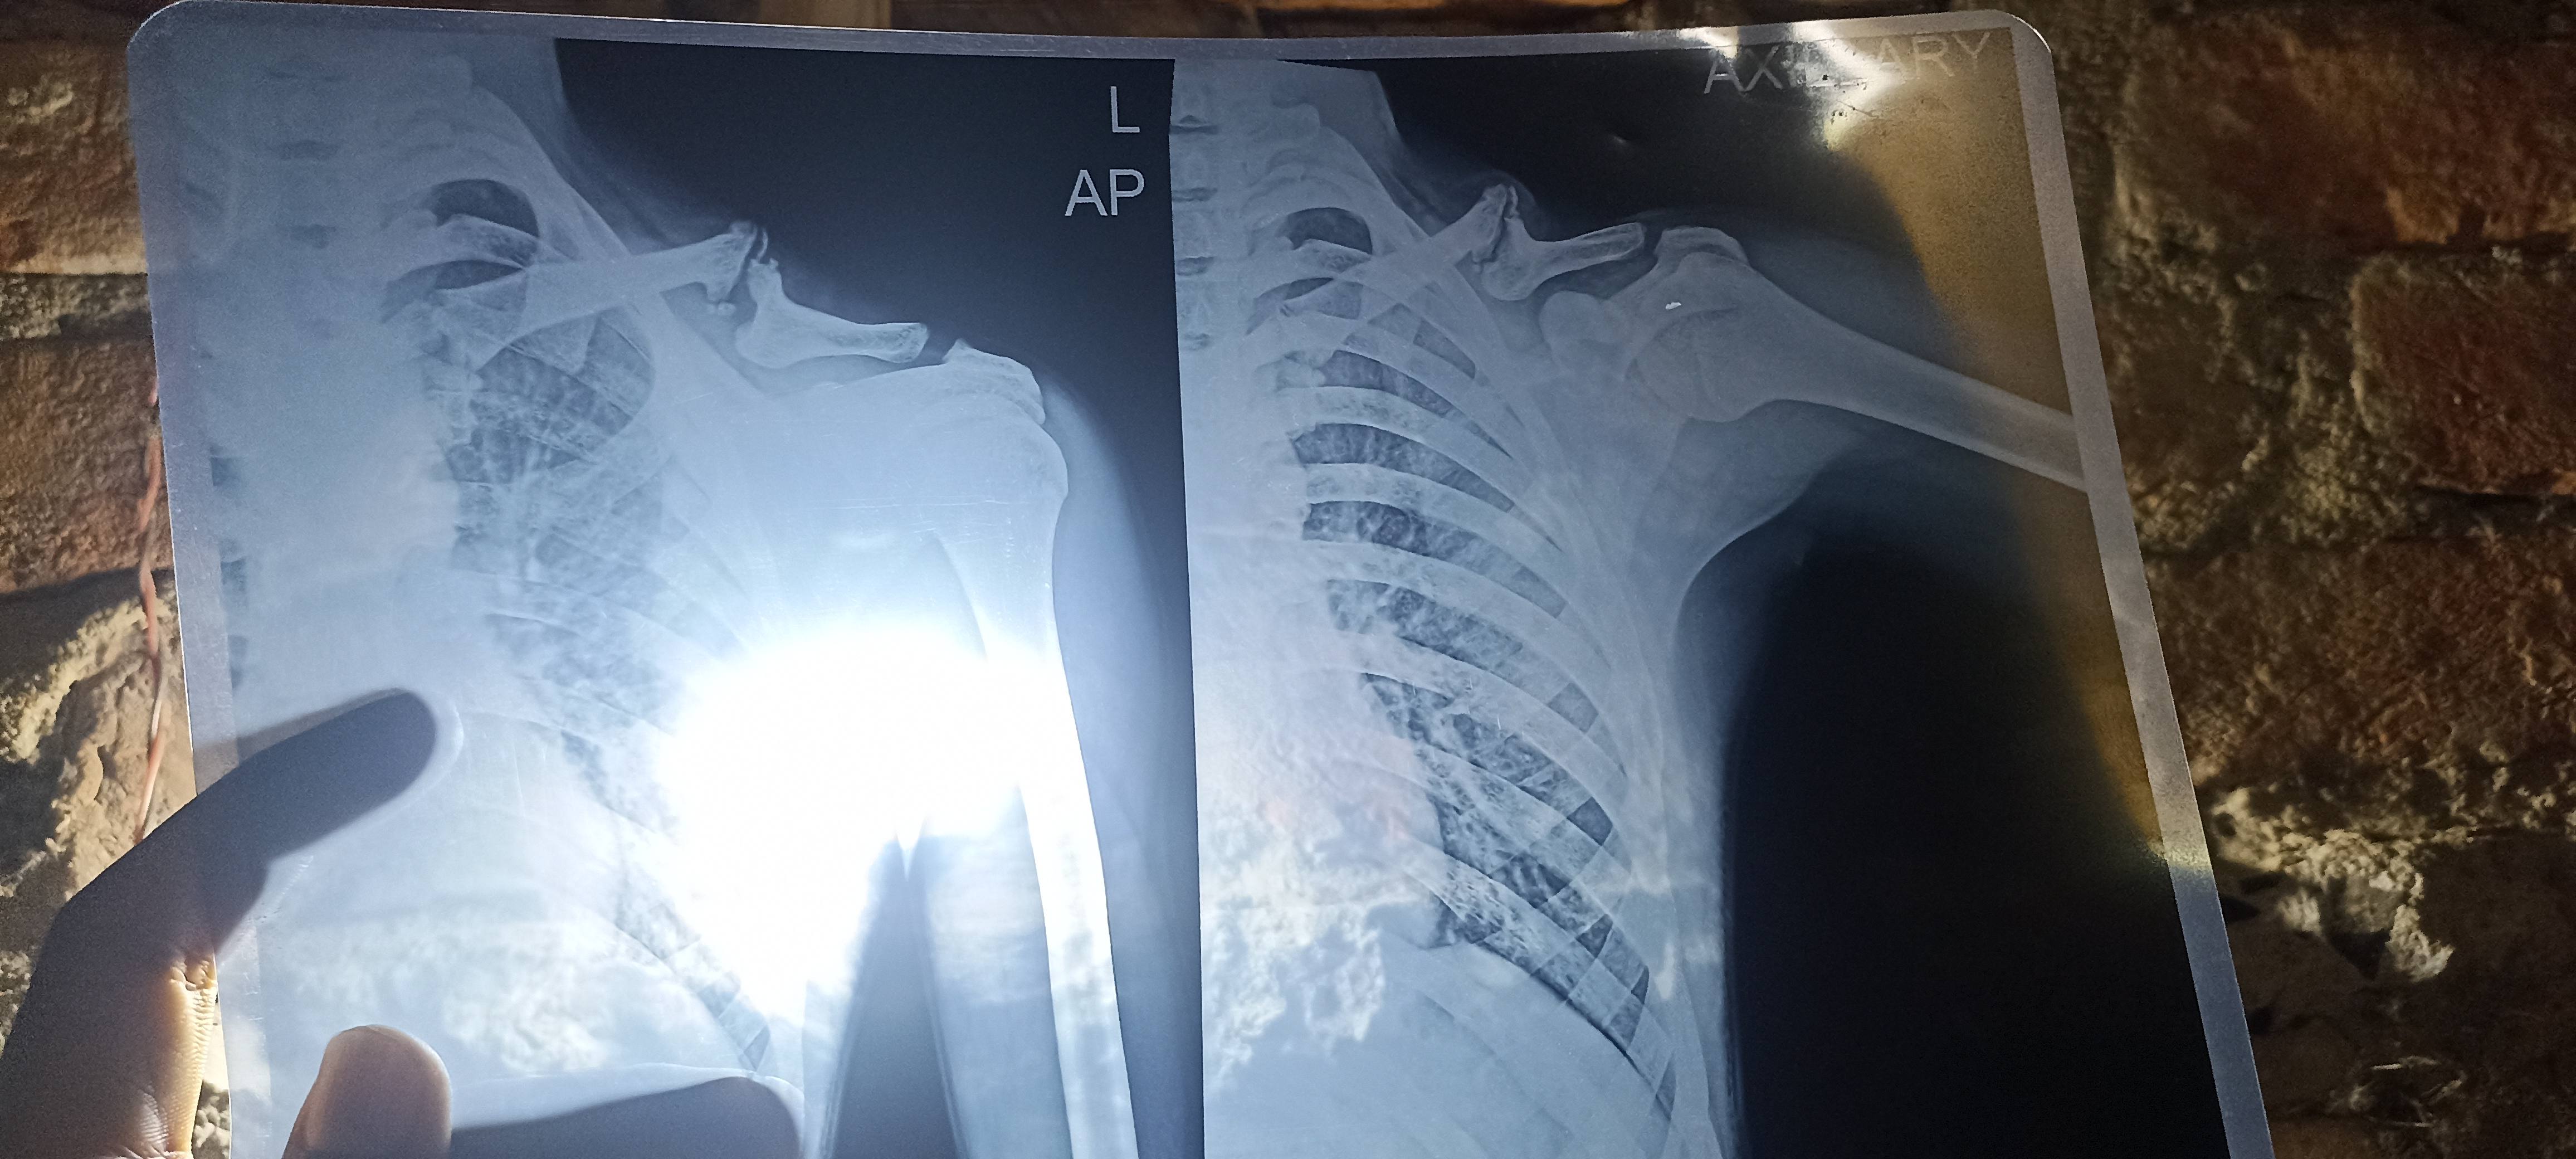

10year old broken This is not joined it but pain how to solve

Sir mera calevical 10 sal pahle fecture ho gaya tha but acche se joined nhi ho paya hai iske karan pain hona stats ho gaya hai please sir your opinion